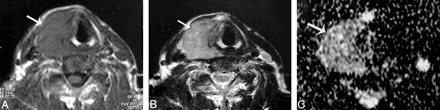

Table 1 illustrates the ADC values of the different histopathologic types of solitary thyroid nodules in this study. The ADC value of the adenomatous nodules ranged from 1.1 to 1.9 × 10−3 mm2/s (Fig 2). Also, the range of the ADC value of the solid part of the follicular adenoma was 1.2–2 × 10−3 mm2/s (Fig 3). The thyroid cysts (Fig 4) revealed the highest mean ADC value (1.9 ± 0.38 × 10−3 mm2/s) apart from 1 patient with hemorrhagic cyst (Fig 5), whose ADC value was 0.5 × 10−3 mm2/s, simulating malignant lesions. The malignant thyroid nodules showed lower ADC values (Figs 6 and 7). The mean ADC value of papillary carcinoma was 0.68 ± 0.23 × 10−3 mm2/s, and that of follicular carcinoma was 0.77 ± 0.17 ×10−3 mm2/s.

Hemorrhagic thyroid cyst. A and B, Axial T1- and T2-weighted MR images, respectively, showing a small well-defined more or less rounded solitary nodule (arrow) affecting the right thyroid lobe. The nodule is hyperintense on both T1- and T2-weighted images. C, An ADC map image shows low signal intensity of the nodule. The measured ADC value is 0.5 ± 0.07 × 10−3 mm2/s.